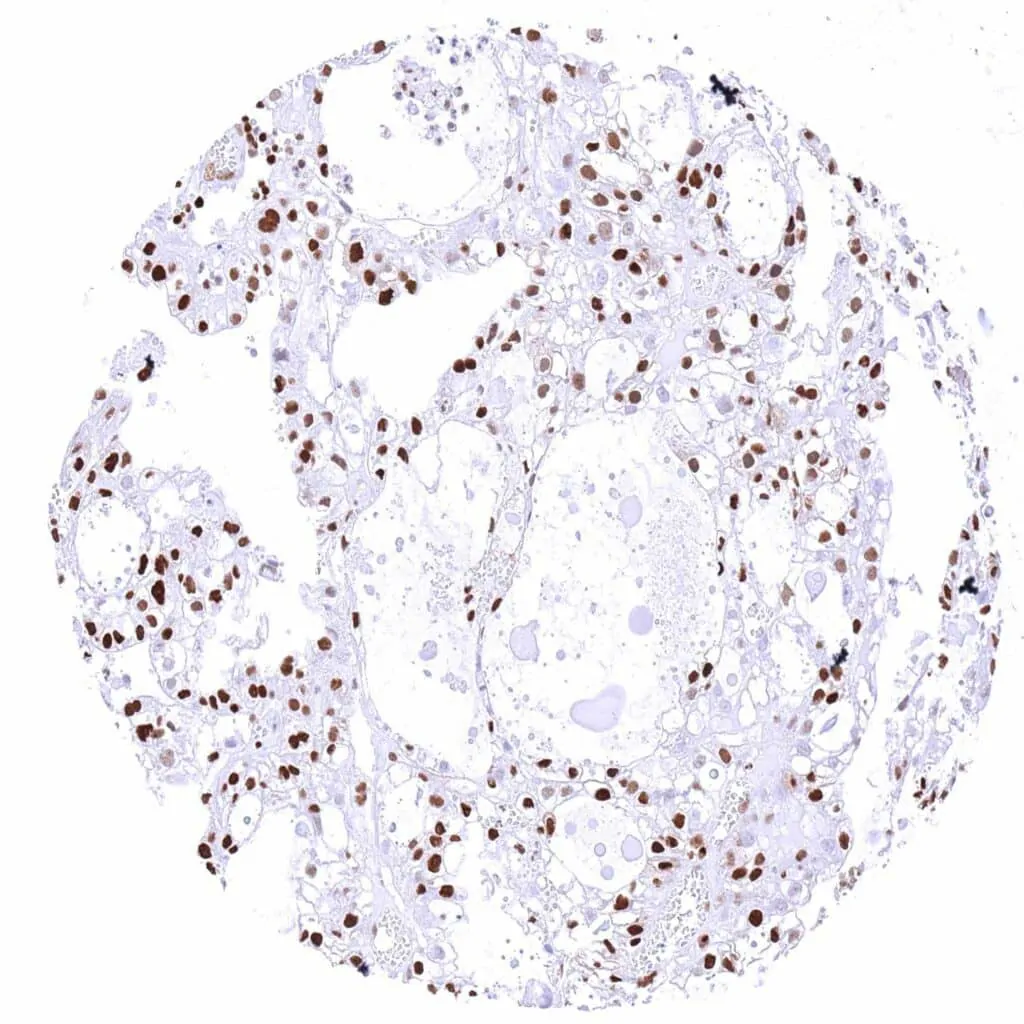

p27 Kip1 antibody [HMV3970] HistoMAX™

Lung – Adenocarcinoma with faint p27 staining of few tumor cells. Strong p27 positivity of stroma cells.